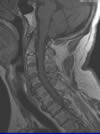

写真Aは同じ患者さんのMRI画像です。 MRI検査と放射線科専門医による診断が、患者さんの現状を詳しく知り、正しい診断によって、適切で安全な治療を提供する鍵となりました。 しかし、X線検査をしていなければ、こういった事は不可能です。